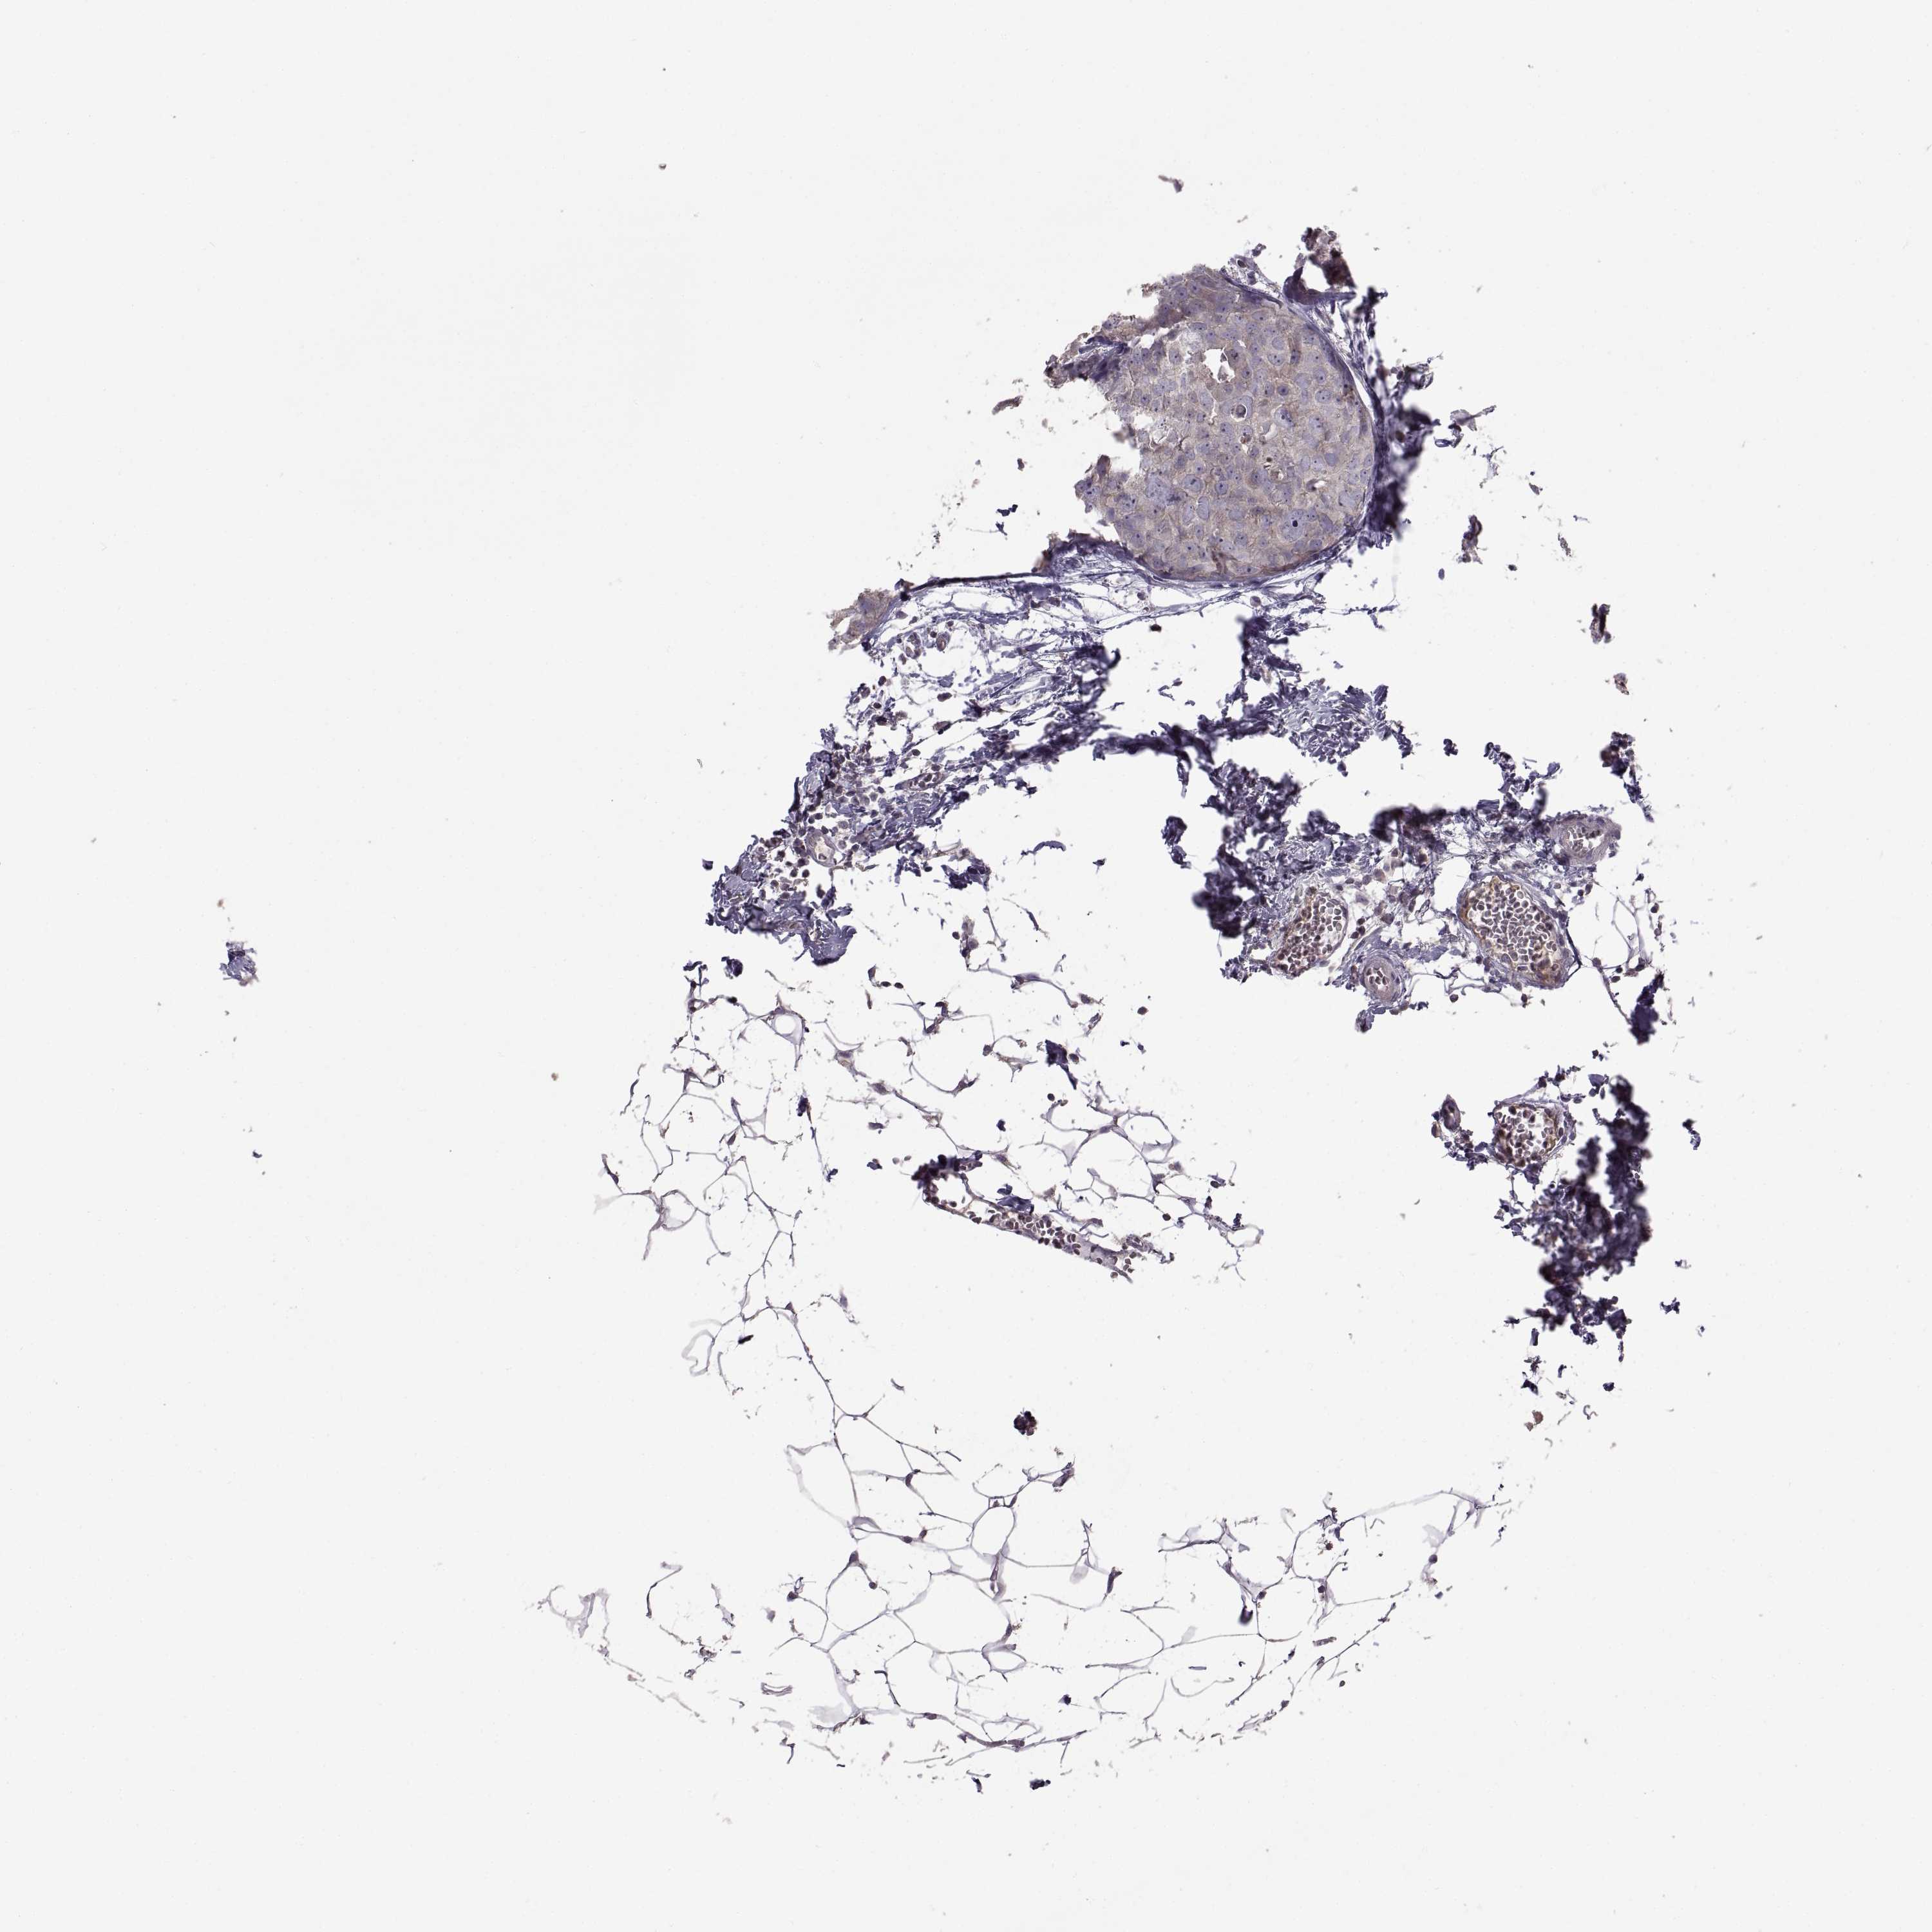

CANCER BREAST CANCER Show tissue menu

BRCA TCGA BRCA VALIDATION PROTEIN EXPRESSION

Breast cancer

Human cancer